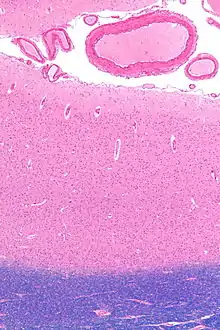

![]() Tissue slice from the brain of an adult macaque monkey (Macaca mulatta). The cerebral cortex is the outer layer depicted in dark violet. Source: BrainMaps.org | |